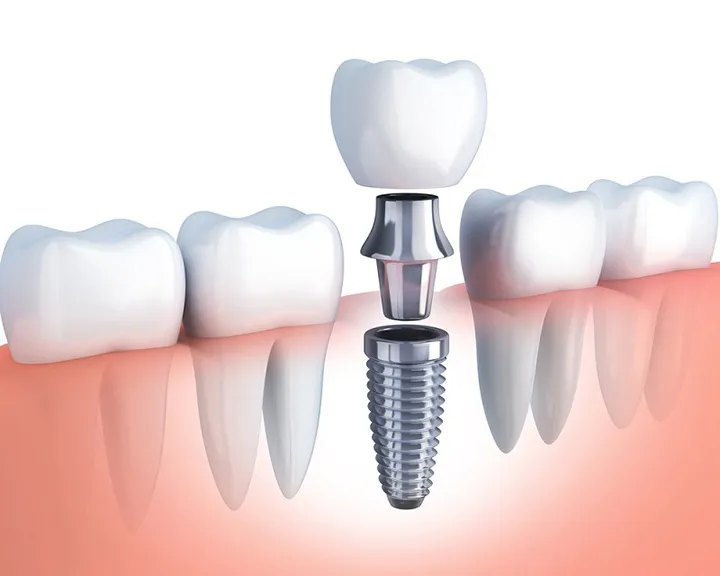

- Bọc răng sứ: Thích hợp khi răng sâu nặng nhưng phần chân răng vẫn khỏe. Bọc sứ giúp bảo vệ cấu trúc răng và phục hồi chức năng ăn nhai.

- Nhổ răng: Răng sâu quá nghiêm trọng, không thể bảo tồn. Lúc này bác sĩ sẽ chỉ định nhổ bỏ răng để tránh sâu lan sang các răng kế cận.